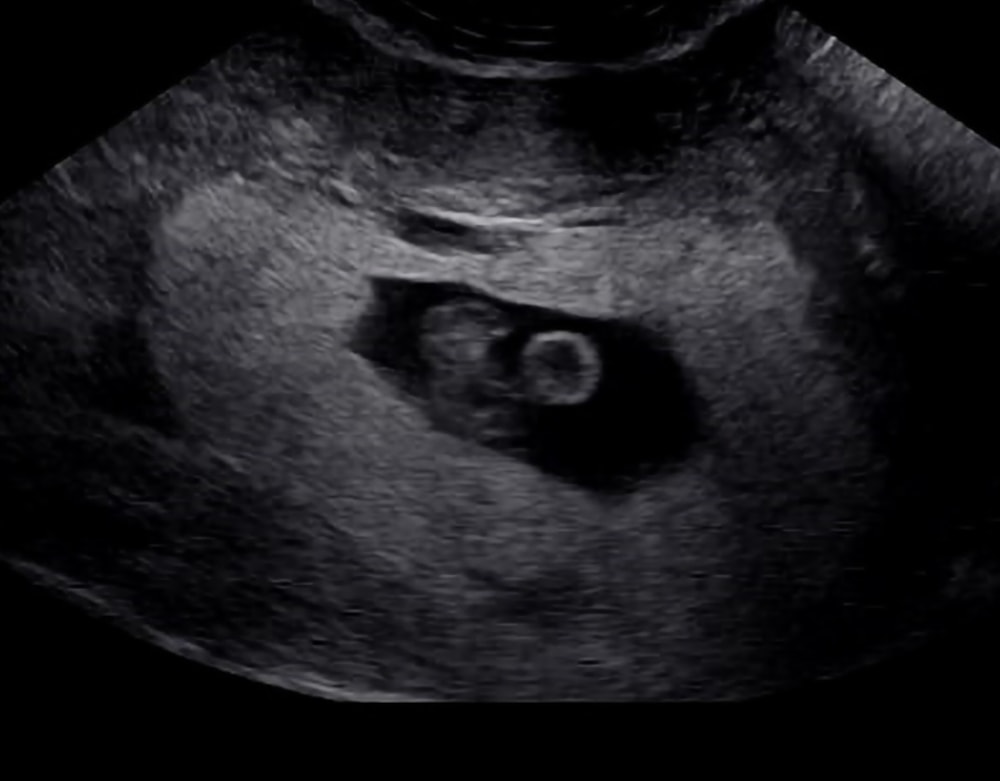

Результаты УЗИСлева эмбриошка) сверху голова. Справа круглое, это жёлтый мешочек)

Срок по узи 6н6д. Идём в срок 🤞

Ктр 8,5 мм ❤️❤️❤️

ЧСС 139❤️❤️❤️